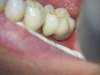

Voici un cas d'extraction d'une molaire, suivie par la pose d'un implant dans la même séance. Molaire de gauche en bas : perforation et kyste entre les racines.

Un résultat qui rend à cette patiente une vraie dent pour la mastication et le sourire.

Voilà un résultat très satisfaisant.